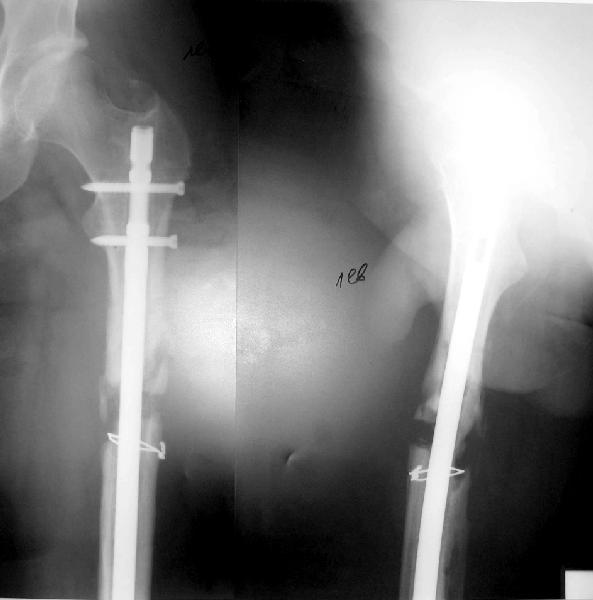

Пациент попал под наше наблюдение через 3 недели после первого остеосинтеза (фото 1). Учитывая, нестабильность остеосинтеза, выстоящий стержень закрыто перештифтовали (фото 2), через 3 месяца динамизация. К 5 месяцам имели укорочение 2 см, при том, что динамический винт стал статическим. От дальнейшей динамизации отказались, учитывая наличие контакта между фрагментами и возможность прогрессирования укорочения. К 1,5 года сращение не достигнуто (фото 3). Удалили гвоздь, выполнили дистракционный остеосинтез с целью стимуляции остеогенеза и компенсации укорочения (фото 4), потом закрыто перештифтовали после рассверливания (фото 5). На сегодняшний день, через 4 месяца после последней операции (фото 6) признаков регенерата нет, длина восстановлена, ходит без дополнительной опоры.

Возможные варианты: 1)подождать - однако регенерата не заметно 2)Снова потерять длину (динамизация, компрессирющий остеосинтез на этом гвозде, после перепроведения проксимальных винтов и копрессирующей заглушки, восстановление длины после сращения) 3)Костная пластика